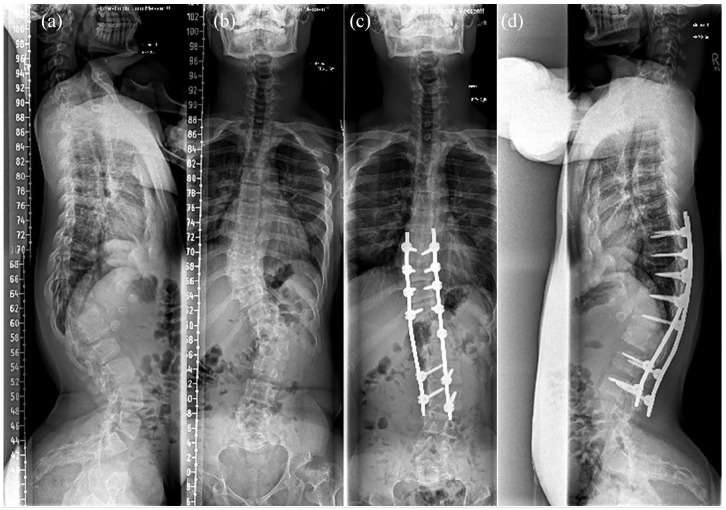

软骨发育不全症是一种最常见的遗传性矮小,是由成纤维细胞生长因子受体 3 基因突变引起的。软骨发育不全症的典型临床特征包括身材矮小、根茎发育不全、关节过度松弛、脊柱畸形和上下肢畸形。后者是最先进的矫形治疗方案所面临的挑战之一,并极大地加重了软骨发育不全患者的疾病负担。在手术干预方面,应考虑多学科术前个体决策。目前已开发出治疗软骨发育不全的新药物,其中一些已在多个国家获准用于临床。虽然有关软骨发育不全的研究文章数量正在迅速增加,但仍有许多未知或有争议的矫形课题。此外,鉴于新的医学发展对生长和潜在的其他影响有所改善,矫形治疗(如引导生长、肢体延长和畸形矫正)的时机和算法需要重新评估。虽然站立高度是医学治疗的主要研究重点,但全面评估这种多因素疾病的矫形参数也至关重要。目前对软骨发育不全患者的治疗需要专门的多学科中心提供过渡性护理和个体矫形咨询。

Achondroplasia, the most common form of inherited disproportionate short stature, is caused by mutations in the fibroblast growth factor receptor 3 gene. The typical clinical features of achondroplasia include short stature, rhizomelic disproportion, joint hyperlaxity, spinal deformity and deformity of the upper and lower limbs. The latter are among the challenges of state-of-the-art orthopaedic treatment plans and significantly contribute to the burden of the disease in individuals with achondroplasia. Multidisciplinary preoperative individual decision-making concerning surgical interventions should be considered. New medical treatments for achondroplasia have been developed and (some) have been approved for clinical use in several countries. While the number of research articles on achondroplasia is increasing rapidly, many unknown or controversial orthopaedic topics remain. Furthermore, in view of new medical developments with improvements in growth and potentially other effects, the timing and algorithms of orthopaedic treatments (e.g. guided growth, limb lengthening and deformity correction) need to be re-evaluated. While standing height is the primary research focus in medical therapy, it is crucial to comprehensively assess orthopaedic parameters in this multifactorial disease. The current treatment of patients with achondroplasia requires specialised multidisciplinary centres with transitional care and individual orthopaedic counselling.